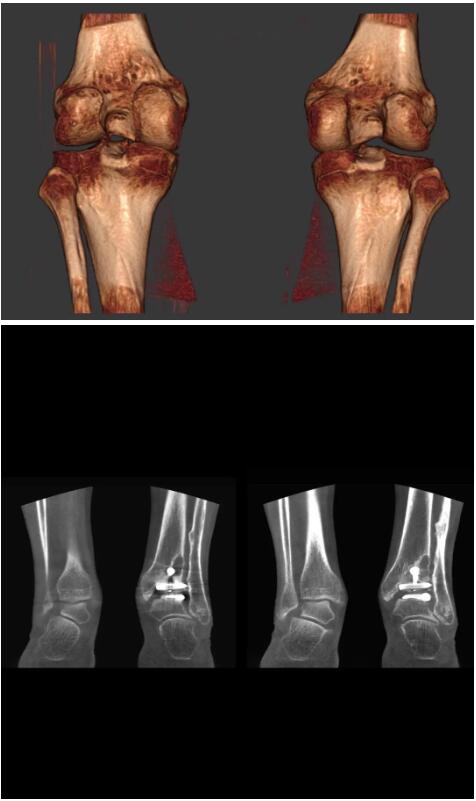

以下是這些“特立獨(dú)行”的CT所拍出來的圖像: